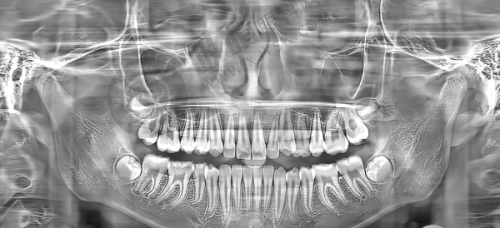

数字化种植牙技术突出:常熟明日口腔医院以数字化诊疗为核心,构建了精良的种植牙体系。医院采用3D口腔CT扫描与数字化设计系统,实现了“可视化种植”。在手术前,医生可以通过精细的扫描和详细的设计,清晰地了解患者口腔的骨骼结构、神经分布等情况,制定出个性化的种植方案。对于骨量不足的病例,医院还提供骨增量技术和穿颧穿翼板种植等解决方案。这意味着即使患者的口腔条件较为复杂,也能在该医院找到合适的种植方法,大大提高了种植牙的成功几率。